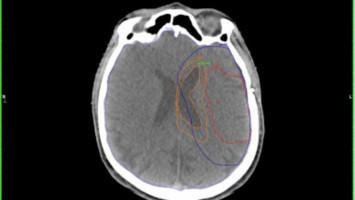

Para caracterizar estos nuevos actores, los investigadores utilizaron células de glioblastoma derivadas de pacientes, lo que les permitió estudiar resultados genéticos y fenotípicos similares a los resultados reales de los pacientes.

Las células se estudiaron tanto in vitro como in vivo mediante su implantación en los cerebros de ratones de laboratorio.